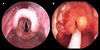

Qual o diagnóstico?

MASTOIDITE AGUDA = COMPLICAÇÃO DA OMA

- Hiperemia retroauricular

- Dor retroauricular

-

EDEMA retroauricular

- Desaparecimento do sulco

- Deslocameno anterior do pavilhão